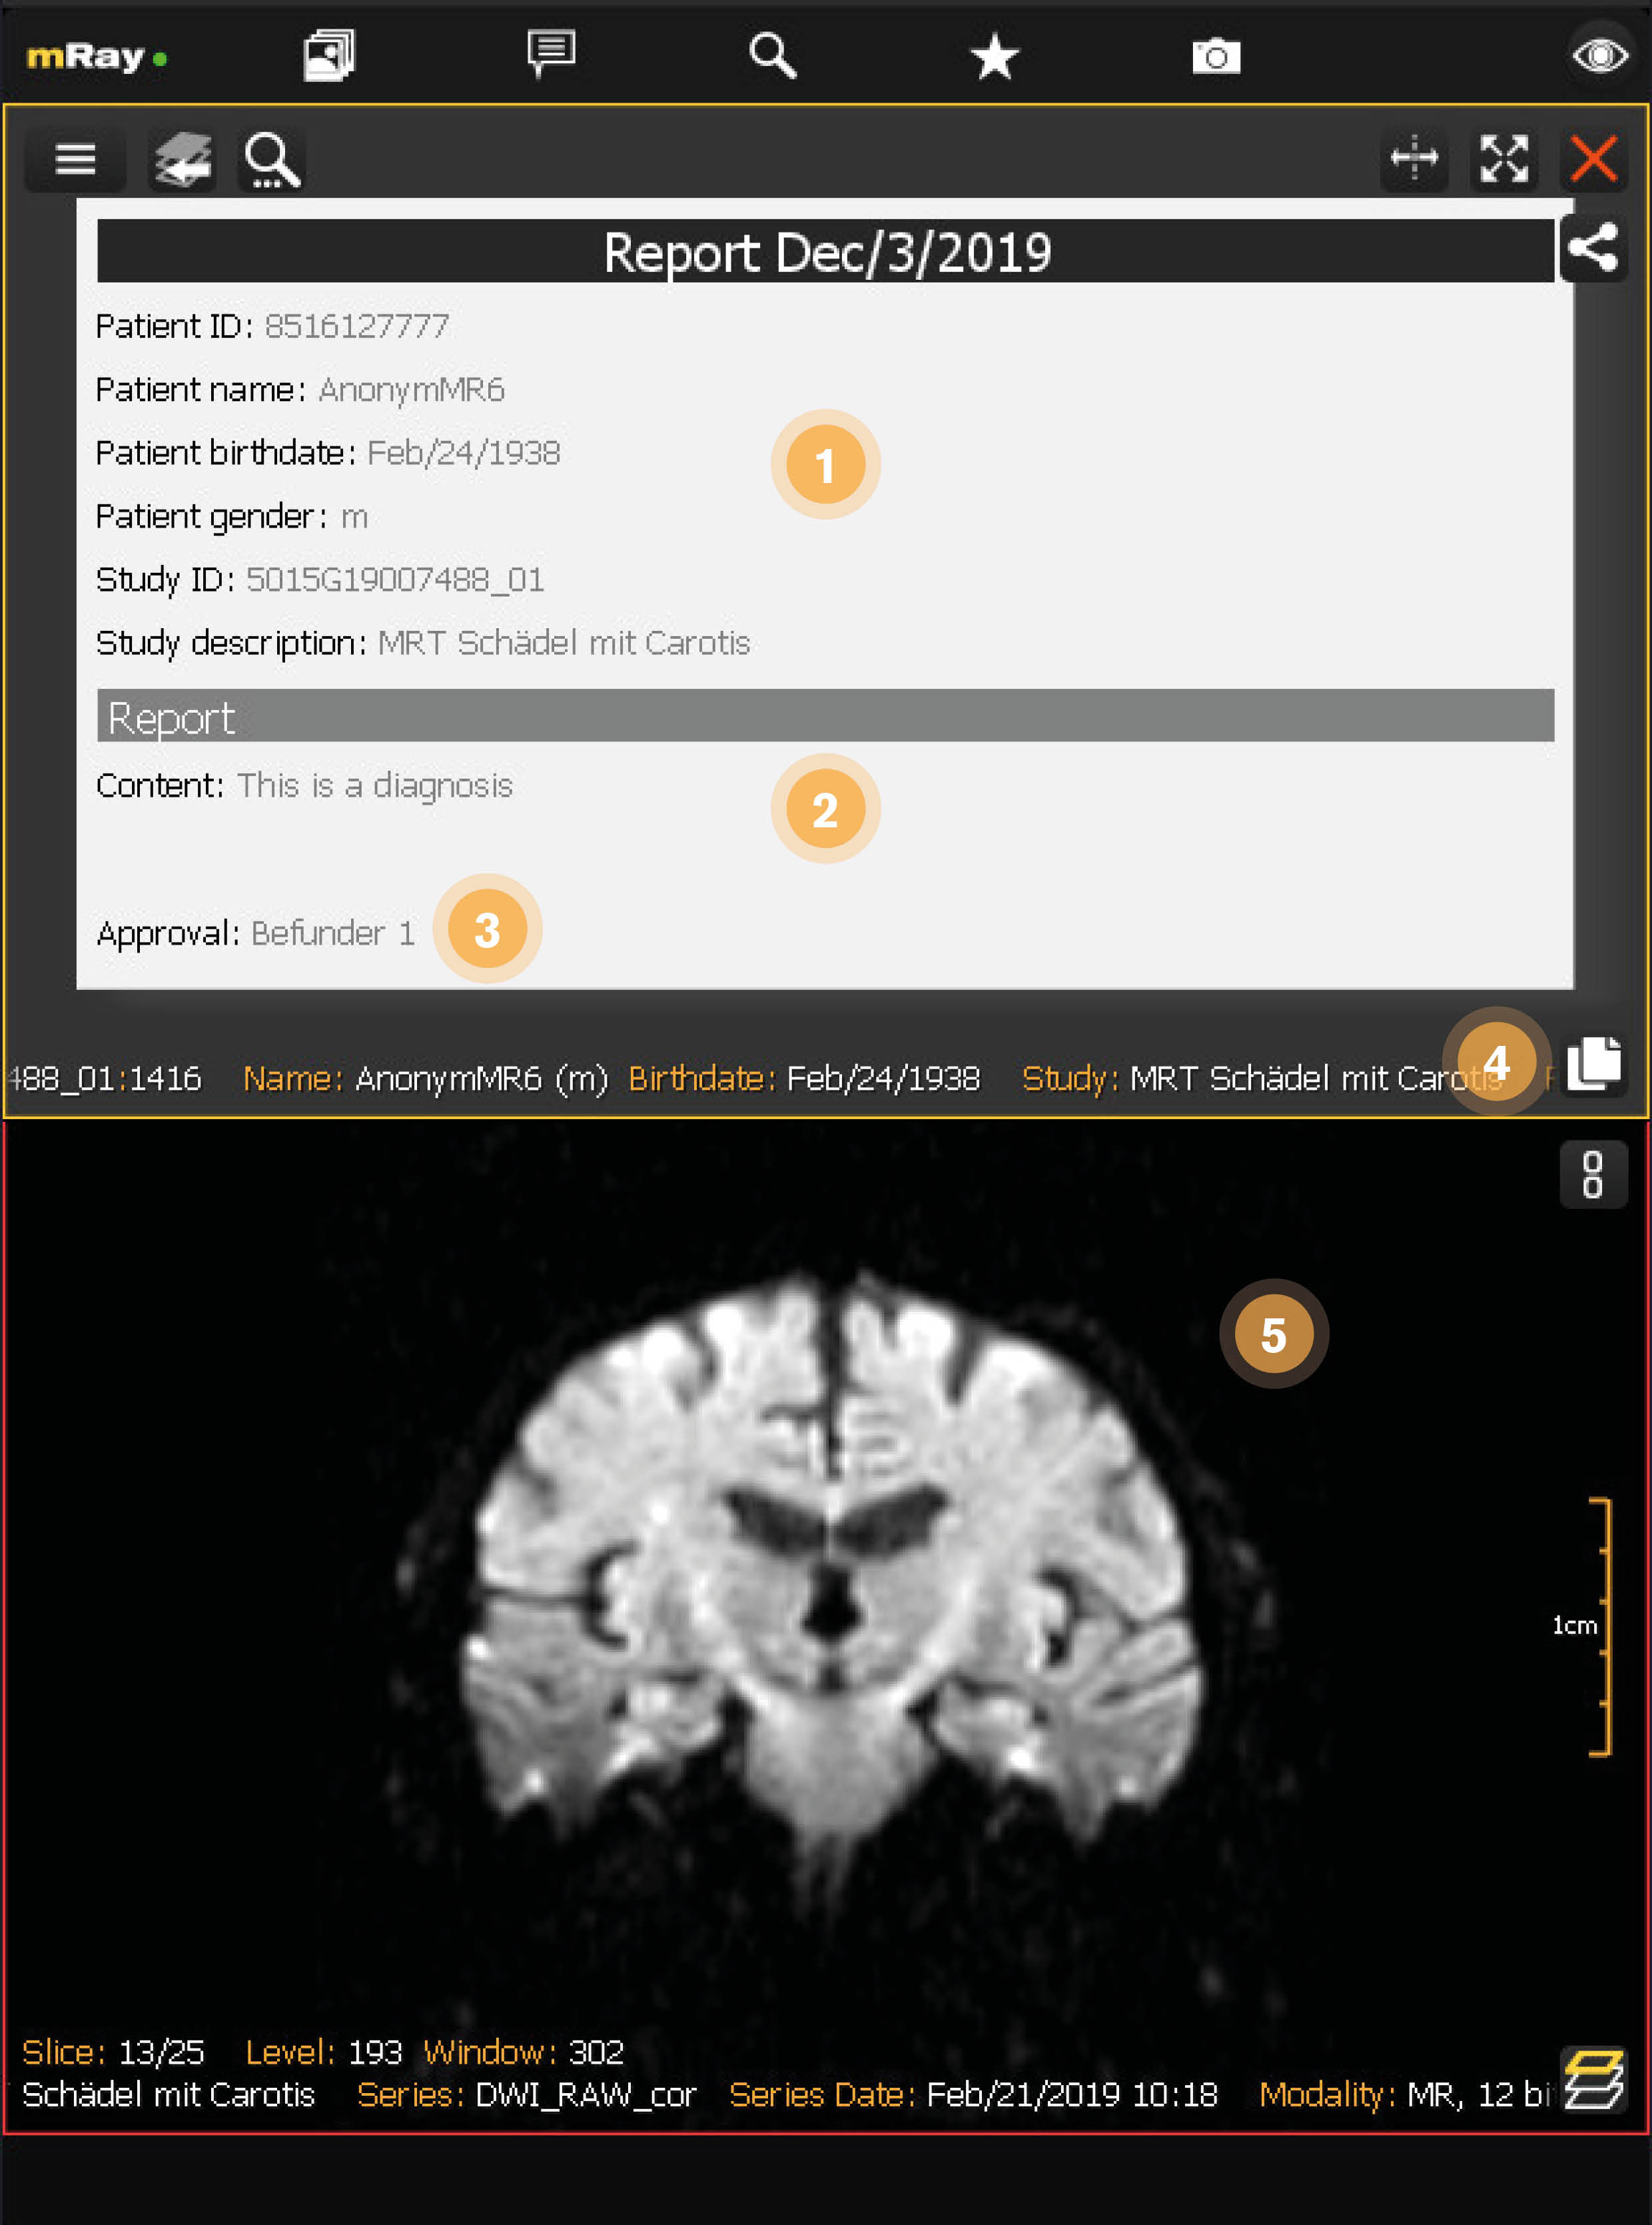

12.5. Berichtansicht

Nachdem der Entwurf freigegeben wurde, ist er nicht mehr modifizierbar und der Entwurf-Status wurde entfernt. Siehe Finaler Bericht.

-

Bericht Zusammenfassung: Zeigt alle Informationen über den geöffneten Bericht an.

-

Bericht Inhalt: Der Text der zu dem geöffneten Bericht hinzugefügt wurde.

-

Bericht Freigabe: Zeigt den Benutzer an, welcher den Bericht freigegeben hat.

-

Inhalt kopieren: Fügt den Inhalt des Berichts in die Zwischenablage ein.

-

Zugehörige Studie: Zeigt die verknüpfte Studie an.

|

Freigegebene Berichte können automatisch in das PACS eingespielt werden, wenn ihr mRay Server diese Funktion unterstützt. Bitte kontaktieren Sie ihren mbits Support für weitere Informationen. |